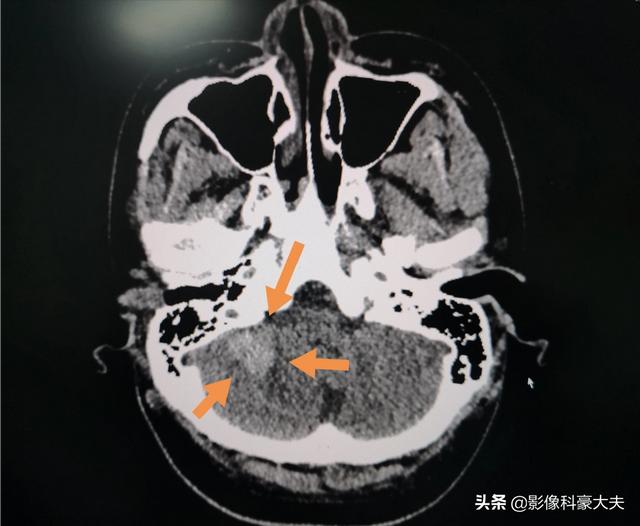

これは22歳の急性白血病の若者の小脳出血で、8分以内に報告書を出しました。

急性期や重症の患者もいる。例えば、大量脳出血、大量脳梗塞、気管異物、肝・脾挫傷、子宮外妊娠出血、大動脈梗塞、重症肺炎など、一刻を争う救命が必要な場合である!このような患者を診察した後、医師は専門医を手配して治療を優先し、最短時間で報告書を発行し、主治医に電話で通知し、できるだけ早く適切な処置を施し、蘇生成功の望みを高める!。

例えば、脳出血の疑いが強い患者の場合、頭部CTを撮った後、比較的早く患者家族に報告書が書き上げられる。この場合、患者の状態が重篤であり、頭部CTの結果が非常に重要であるため、多くの場合、報告書が迅速に患者に渡されるのは理解できる。